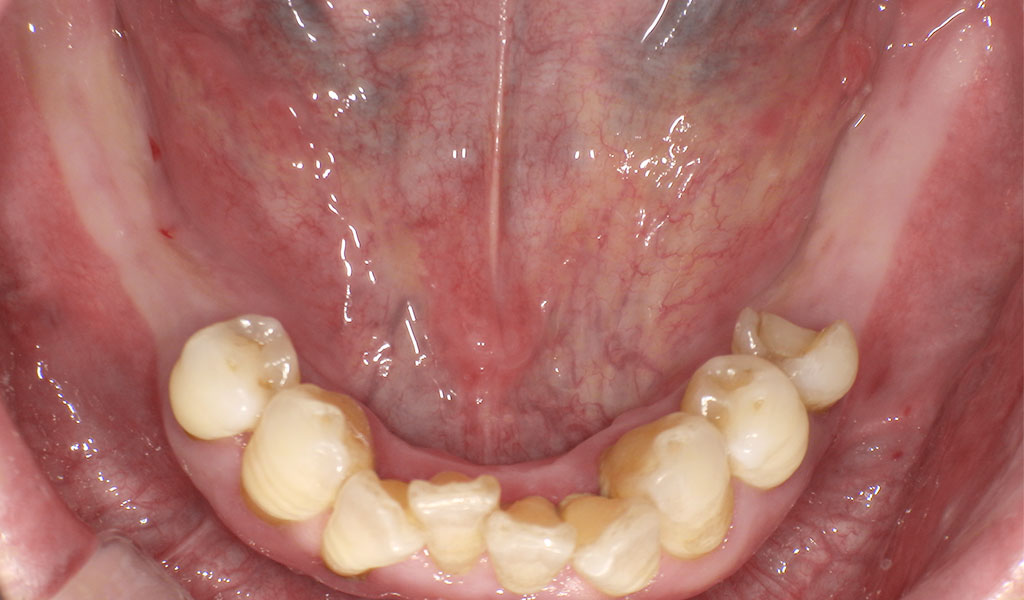

Before(左下6,7番、右下5,6,7番)

60代男性・横浜市在住。歯周病により歯がぐらついていたため、当院にて左上6番、左下6,7番、右下5,6,7番を抜歯後、インプラント治療。人工歯はジルコニア人工歯。スクリューリテインにて固定しました。歯周病菌の数が多いため、歯周内科治療も実施しました。